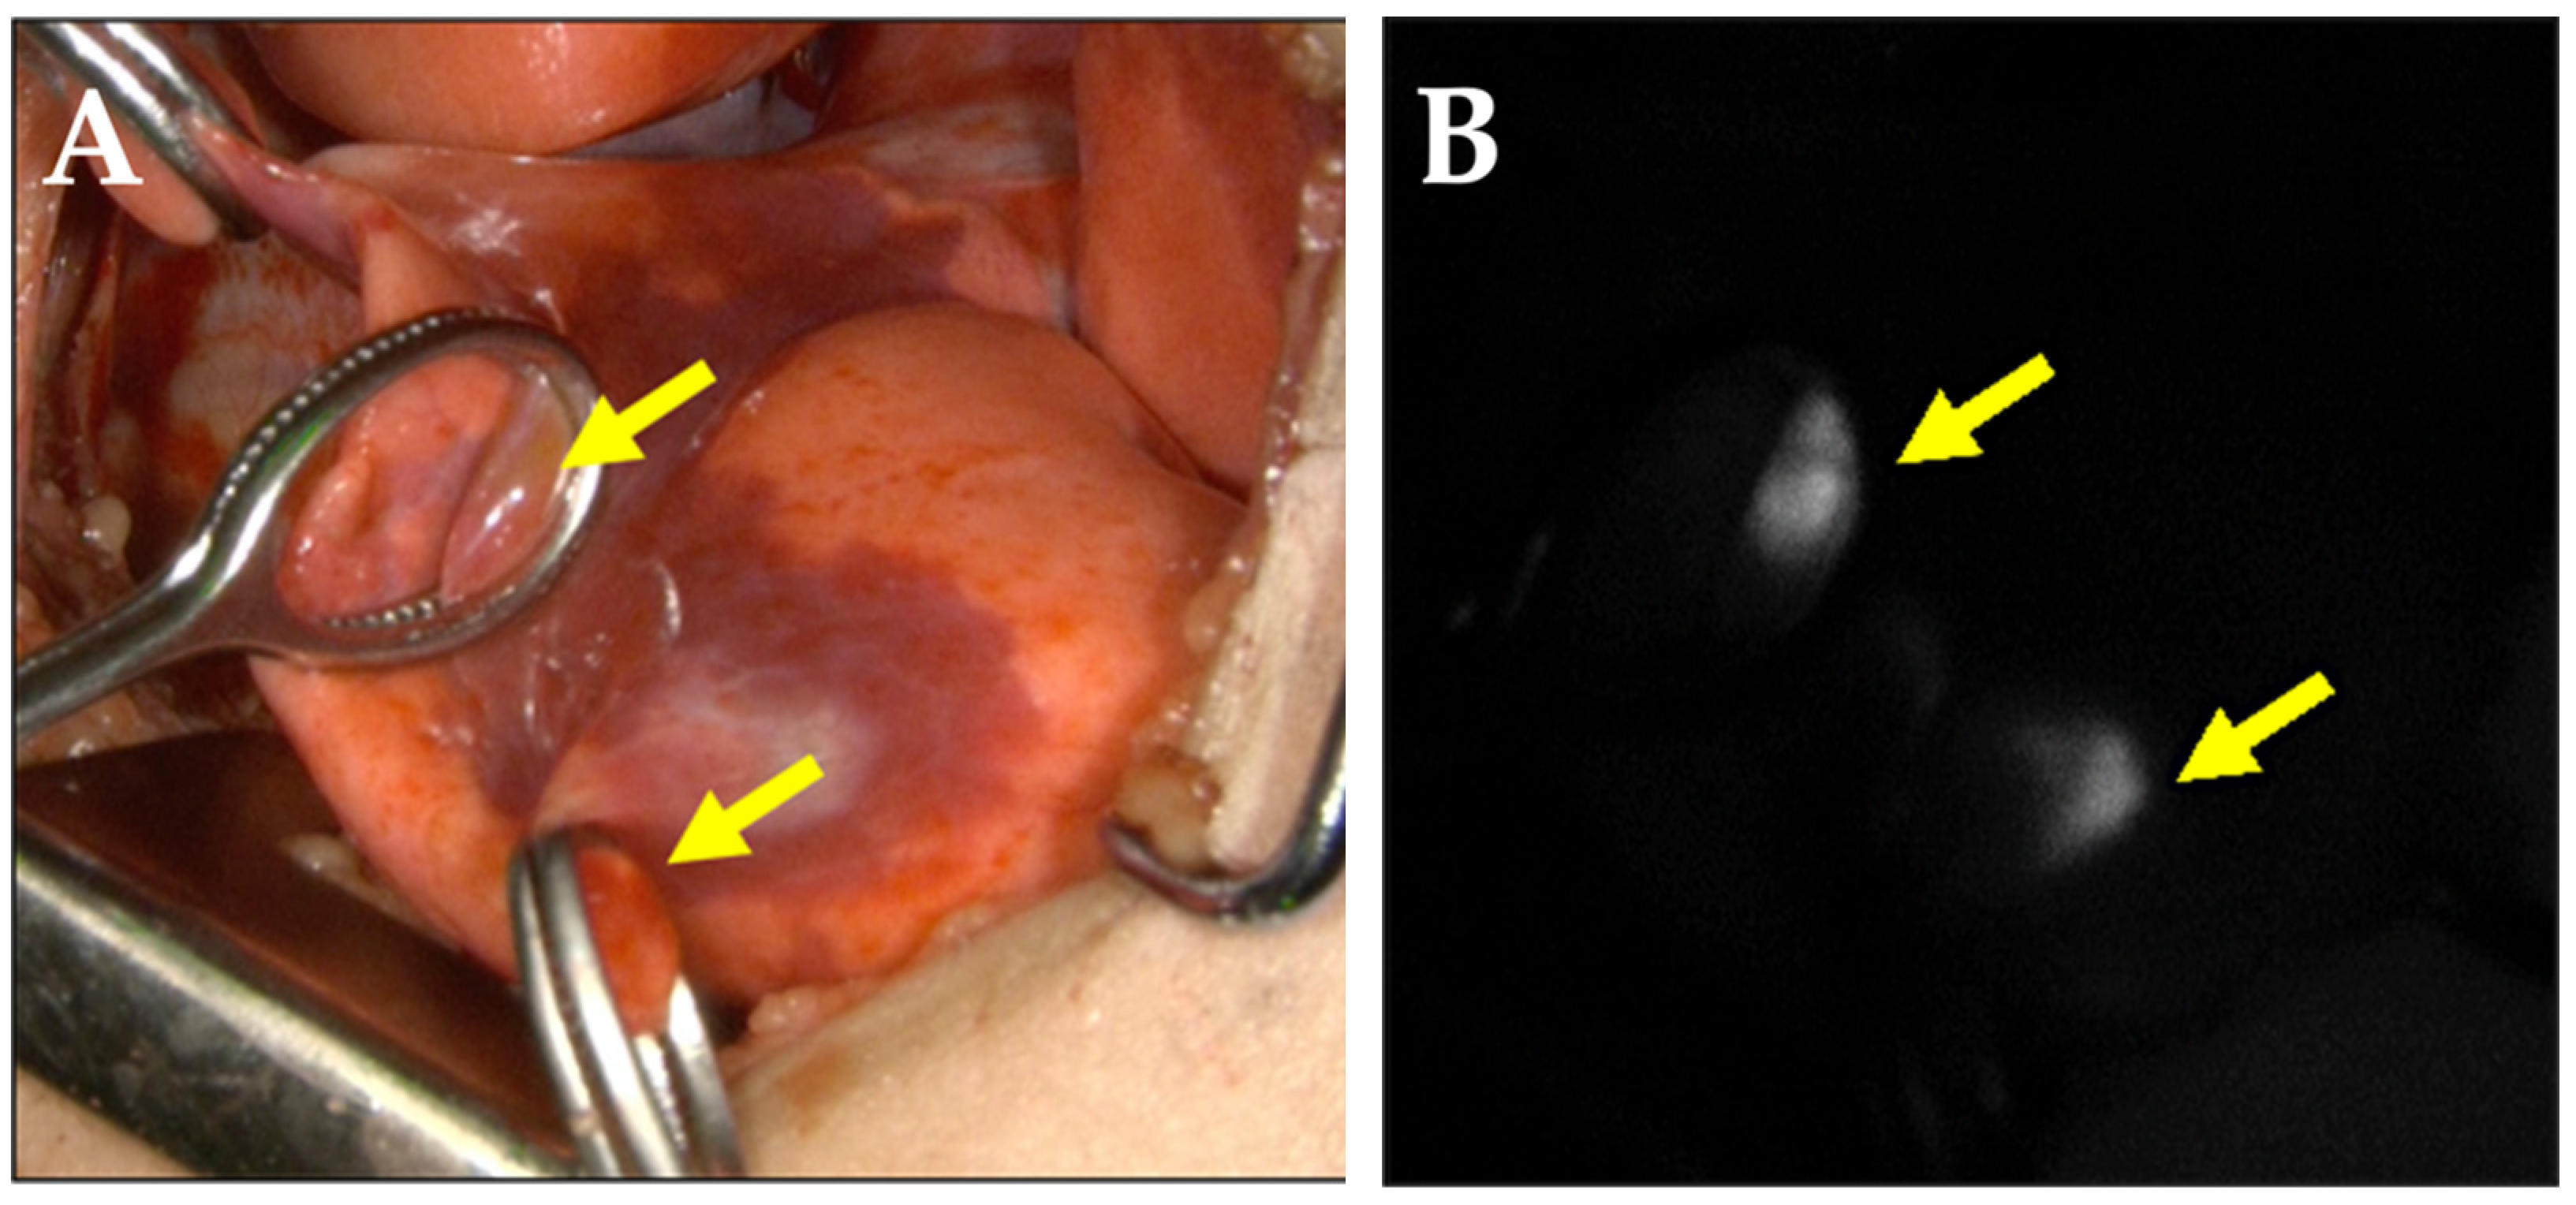

2. Case Report